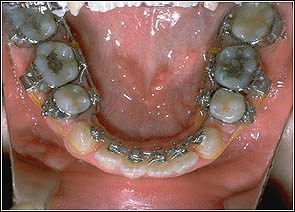

STEP 1. Leveling

TMA018, 0175*0175